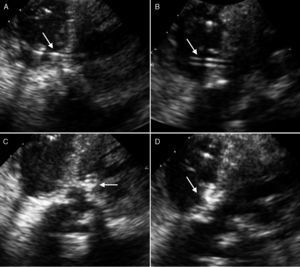

The postoperative course was indolent and the patient developed complete atrioventricular block that required implantation of a permanent pacemaker. Transthoracic and transesophageal echocardiography (TEE) led to the diagnosis of a VSD measuring approximately 5mm following myectomy. This defect produced severe pulmonary hypertension (85mmHg) with moderate-to-severe tricuspid insufficiency and a situation of low output (Figure 1). Due to the progressive hemodynamic deterioration and the fact that it was not possible to discontinue inotropic drugs or extubate the patient, the decision was made to close the VSD. Because of the high surgical risk so soon after a recent operation, together with the difficulty associated with a percutaneous intervention, we decided to perform a hybrid procedure. The TEE-guided procedure was carried out in the cardiac operating room. Median sternotomy was performed and, using an 18-gauge needle, a puncture was made through a purse-string suture placed in right ventricular free wall. A short (45cm) 0.035” guidewire was then introduced through the needle. The guidewire was directed toward the VSD and through it. A 7-Fr introducer with the dilator was passed through the defect with utmost care in order to avoid perforating the left ventricular wall. Once the introducer was in place and the dilator withdrawn, a 6/4 Amplatzer Duct Occluder II (AGA Medical Corporation) was loaded into the delivery device and implanted into the VSD by means of the 7-Fr introducer, in accordance with the standard technique (Figure 2). The result was satisfactory; there was a minimal residual shunt in the device and, at the end of the procedure, the pulmonary pressure had decreased from 85mmHg to 40mmHg. The patient was discharged with no complications.

Figure 2. A: passage of the guidewire through the ventricular septal defect following needle puncture of right ventricular free wall. B: position of the introducer after withdrawal of the guidewire. C: placement of the device in the defect with initial release of left disc. D: complete implantation of the device secured to the defect by the discs on either side of the two ventricles.